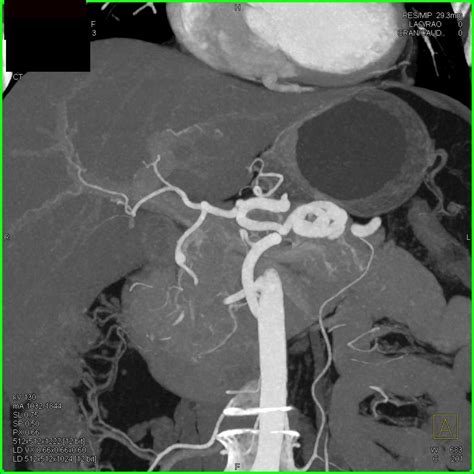

Angiography: Involves injecting a contrast dye into the blood vessels and taking X-ray images. It provides detailed images of the blood vessels and can help plan treatment.

Angiography is particularly useful for planning surgical or endovascular interventions.